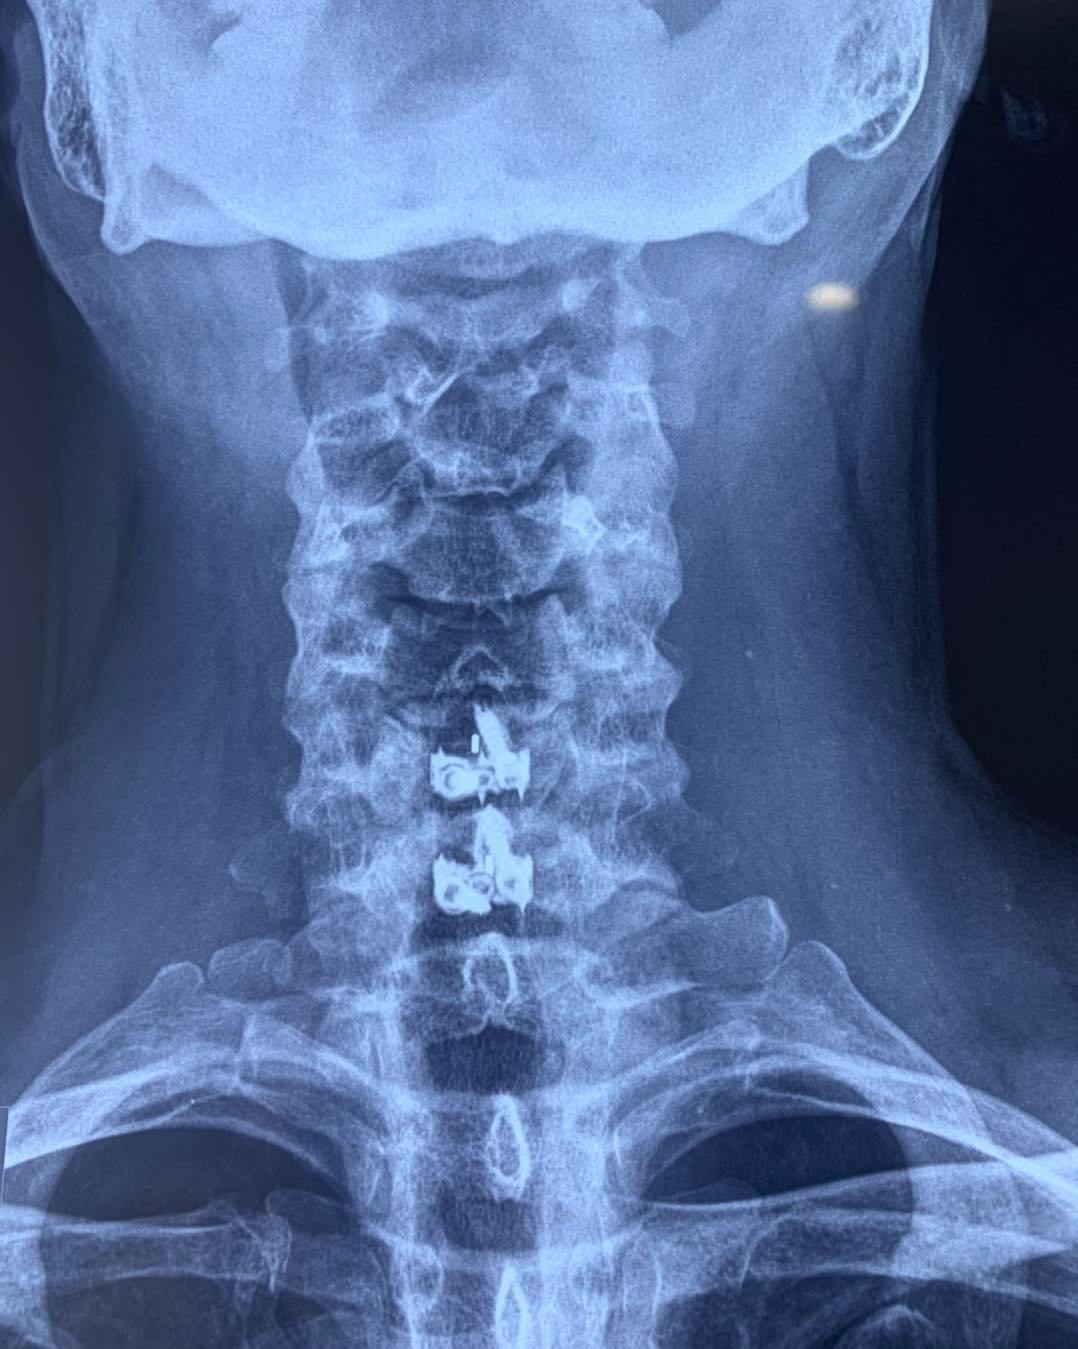

SURGERIES

RESULTS